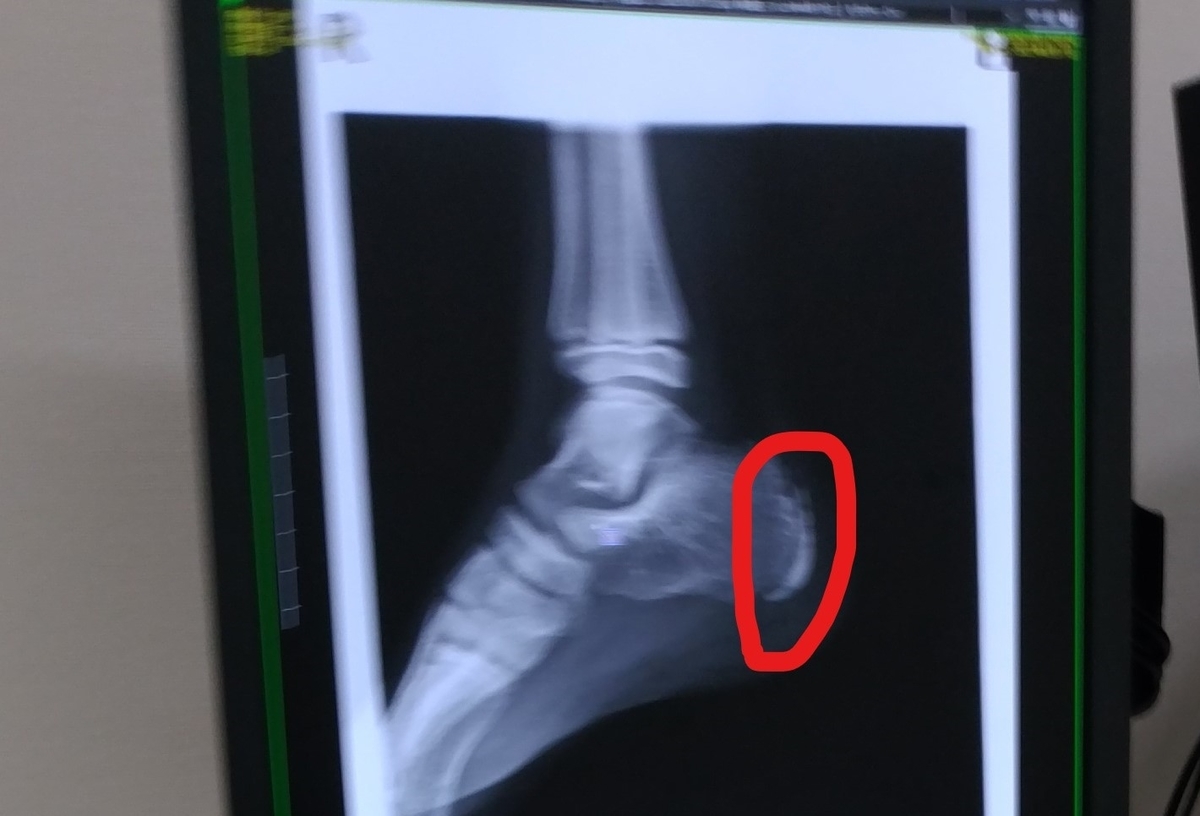

そして、後日整形外科を受診したところ…

息子と整形外科クリニック受診。

やっぱりシーバー病の診断👣

足のレントゲン像でわが子の足の成長を感じる体😅